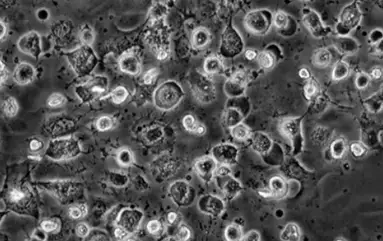

Destroyed cell structure under a microscope after exposure to electrosmog

Connective tissue cells after exposure to electrosmog:

The cell vitality has reduced drastically.